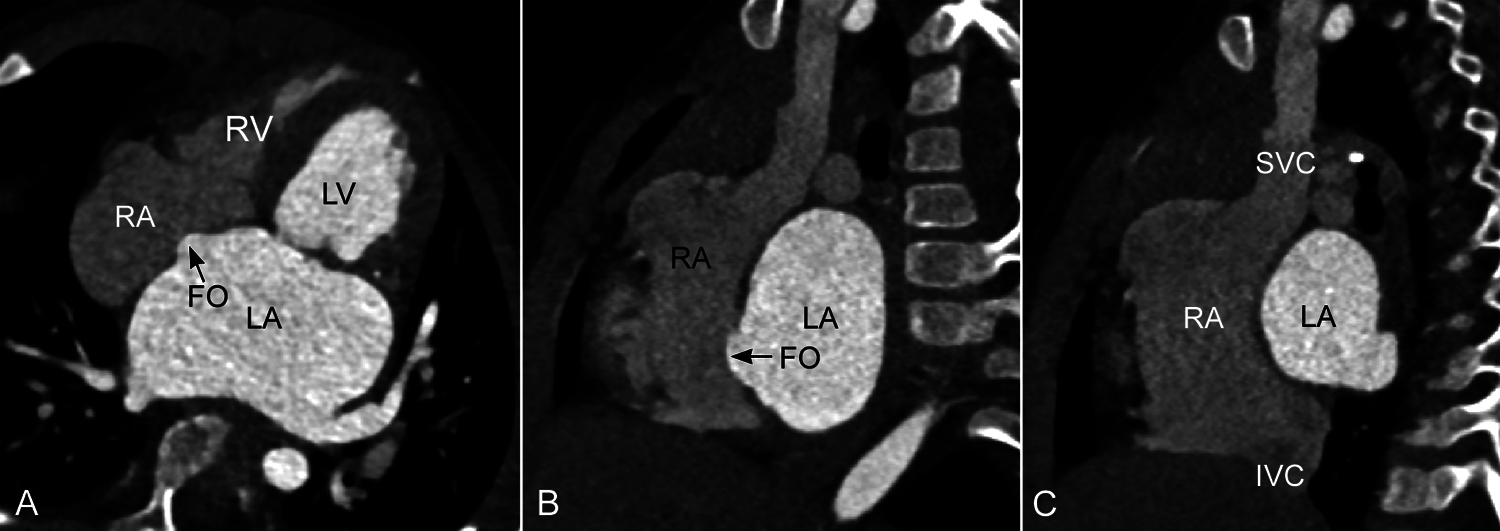

The party wall between the right and left atria consists of the central thin oval area and the peripheral thicker rim that imperceptibly transitions to the atrial free wall and adjoining venous structures (Figs. 1 and 2) [10–12]. As the central thin area is seen as an oval depression from the right atrial side, it is called the fossa ovalis and the surrounding rim is called the limbus of the fossa ovalis. The limbus consists of two thin layers of myocardium and an interposing sliver of fat tissue of variable thickness, all of which appears to be the result of infolding of the atrial wall and epicardial fat (Fig. 2) [10–12]. The intervening fat layer can be particularly prominent in obese individuals, allowing easy understanding of its normal distribution throughout the limbus and the right atrial side of the atrioventricular muscular septum (Figs. 2–4). The limbus is distinctively identifiable superiorly where the free edge of the thin membranous fossa ovalis is fused to the left atrial side of the limbus after birth. The limbus is less prominent or indistinct postero-inferiorly where the fossa ovalis is continuous with the posterior wall of the inferior vena cave (Figs. 1 and 3–A–b) [12–14]. Anteriorly and inferiorly toward the tricuspid valve, the limbus is continuous with the atrioventricular septum (Fig. 2). As most of the limbus is formed by infolding of the atrial wall and epicardial fat, Anderson et al. regard only the floor of the fossa ovalis and the anterior and inferior part of the limbus as the true atrial septum [10–11,13,14]. However, a large part of the interatrial party wall consists of the limbus, while the size of the fossa ovalis varies widely among individuals and can be very small (Fig. 5) [15,16].

Figure 5: Computed tomographic angiograms in 4-chamber plane (A) and parasagittal intercaval or bicaval planes (B and C) from a patient with severe mitral stenosis. The fossa ovalis (FO) is extraordinarily small and bulges into the right atrium (RA) due to an elevated left atrial pressure. There is exaggerated convexity of the party wall between the sinus venarum and the left atrium (LA) in C. The long axes of both superior (SVC) and inferior (IVC) venae cavae are aligned with the left atrial cavity. LV, left ventricle; RV, right ventricle

The interatrial party wall is mostly flat except for the right lateral posterior aspect where the superior and inferior venae cavae form a confluence called the sinus venarum (Fig. 3). The upper part of the sinus venarum is bounded posteriorly by the far-right side of the left atrium to which the right pulmonary veins connect. As the inferior vena cava is more posteriorly located than the superior vena cava, the party wall between the sinus venarum part of the right atrium and the adjacent left atrium–right pulmonary venous confluence is obliquely oriented with a gentle convex curvature forward and downward. Such oblique orientation of the interatrial party wall along the sinus venarum can be best appreciated in the parasagittal intercaval or bicaval imaging plane (Figs. 3A and 6). In this particular plane, the long axis of the inferior vena cava is oriented vertically toward the left atrium across the most inferior part of the interatrial party wall. The orifice of the inferior vena cava is often guarded anteriorly by a prominent membranous flap called the Eustachian valve (Fig. 6B). When present, the Eustachian valve inserts to the anterior inferior aspect of the limbus, while its superior free edge is aligned with the superior part of the limbus that in fetal medicine is named as the crista dividens [11–12,17]. The Eustachian valve is oriented in such a way to allow the inferior vena caval flow streaming into the left atrium through the patent foramen ovale during fetal life [11,17].

Figure 6: Magnetic resonance images in a parasagittal intercaval or bicaval plane from two individuals. The party wall between the right atrium (RA) and left atrium (LA) is convex forward and downward in this plane with the inferior vena caval axis (IVC, large vertical arrow) directed upward toward the left atrium above. The Eustachian valve (Eust.valve) is prominent in B. Note that the Eustachian valve is aligned with the superior part of the interatrial party wall, i.e., the limbus. RPA, right pulmonary artery; SVC, superior vena cava